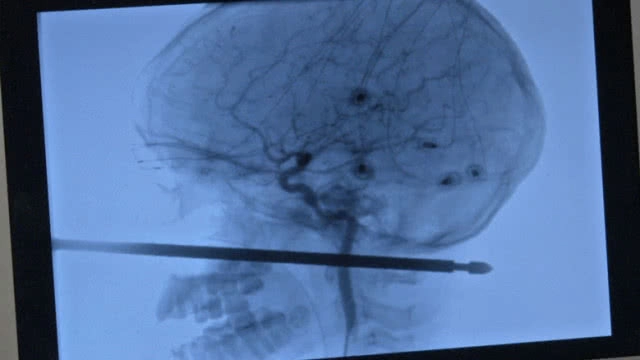

เหล็กแหลมเสียบเข้าแก้มซ้ายใต้ตา ทะลุกะโหลกศีรษะเกือบทะลุคออีกด้าน

การผ่าตัดครั้งนี้ใช้บุคลากรการแพทย์ราว 100 คน ค่อยๆเอาเหล็กแหลมความยาว 1 ฟุตไม่ให้โดนเส้นเลือดออกได้สำเร็จ หมอกล่าวว่าหากทะลุไกลกว่านี้อีก 1 นิ้ว อาจบาดเจ็บสาหัสหรือไม่รอดชีวิต

โคจิ เอเบอร์โซล แพทย์ประสาทศัลยกรรม กล่าวว่าเหล็กแหลมไม่โดนดวงตา เฉียดสมอง และไขสันหลัง นับเป็น 1 ในล้านของการถูกของแหลมความยาว 5-6 นิ้วทะลุใบหน้าจนถึงด้านหลังแล้วไม่โดนส่วนสำคัญที่ว่ามาเลย แต่แทงแทงผ่านพื้นที่น้อยๆในศีรษะใกล้กับเส้นเลือดหลัก "ผมไม่เคยเห็นอะไรที่เสียบเข้าไปลึกแบบนั้นแล้วยังสามารถรอดชีวิตได้ ยังไม่ต้องพูดถึงการรักษาได้จนเกือบหายหรือไม่หาย"